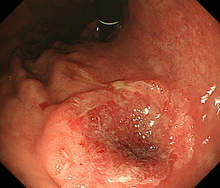

胃がんは、胃の壁の最も内側にある粘膜内の細胞が、何らかの原因でがん細胞になって無秩序に増殖を繰り返すことで生じます。胃がん検診などの検査で見つけられる大きさになるまでには、通常何年もかかるといわれています。胃がんの診断には胃の内側から内視鏡(胃カメラ)で観察することにより診断が可能であり、胃がんの部分がイボのように盛り上がったり、潰瘍を形成し陥凹している部分、色調の変化した部分などを詳しく観察します。生検検査でがん細胞を認めると診断が確定します。胃がんの内視鏡写真を提示します(図1)。

がん細胞の増殖の仕方によって「分化型胃がん」と「未分化型胃がん」に分かれます(図2)。分化型胃がんでは、もとの正常な細胞の特徴を残したまま塊を作って大きくなります。一方、未分化型胃がんは、もとの細胞の構造がほとんど見られずバラバラに広がり、がんの範囲も分かりにくいです。とくに未分化型胃がんのなかで、粘膜に発生した癌が表面を広がらないで粘膜の深いところを這うように広がって行くタイプ(スキルス胃がん)では診断がつきにくく、かなり進行しないと見つかりにくい場合もあります。